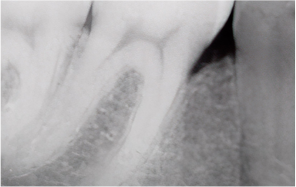

치주질환이란?

‘잇몸병’이라고 불리는 치주염은

잇몸과 잇몸뼈(치조골)를 파괴하는 대표적인 질환입니다.

초기에 단순히 잇몸이 붓고

피가 나는 수준에서 시작하지만,

방치하면 치조골이 점차 흡수되어

결국 치아를 발치해야 하는 상황까지 이어질 수 있습니다.